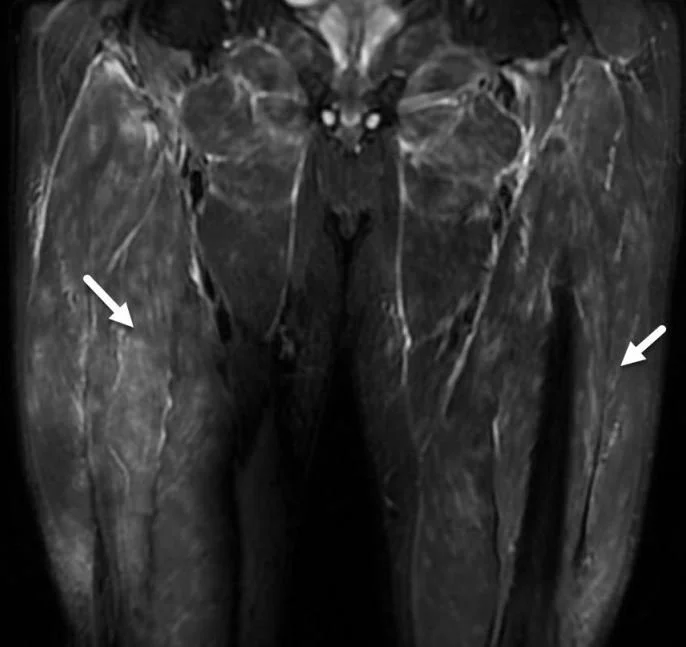

An MRI shows diffuse myositis. What two tests are still needed?

Bilateral muscle edemal